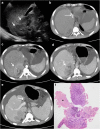

Objectives: We aim to illustrate the multimodal imaging spectrum of hepatic involvement in tuberculosis (TB). Whilst disseminated tuberculosis on imaging typically manifests as multiple small nodular lesions scattered in the liver parenchyma, isolated hepatic tuberculosis remains a rare and intriguing entity.

Methods: Indubitably, imaging is the mainstay for detection of tubercular hepatic lesions which display a broad spectrum of imaging manifestations on different modalities. While sonography and computed tomography (CT) findings have been described in some detail, there is a paucity of literature on magnetic resonance imaging (MRI) features. Due to a significant overlap with other commoner and similar appearing hepatic lesions, hepatic tuberculosis is often either misdiagnosed or labelled as indeterminate lesions. This article is a compendium of cases highlighting the spectrum of imaging patterns that can be encountered in patients with isolated primary hepatic tuberculosis as well as disseminated (secondary) disease. Rare patterns of primary disease such as tubercular cholangitis, hypervascular liver masses, and those with vascular complications are also illustrated and discussed.

Teaching points: • Hepatic TB has myriad imaging manifestations and is often confounded with neoplastic lesions. • Imaging patterns include miliary TB, macronodular TB, serohepatic TB and tubercular cholangitis. • Concurrent splenic, nodal or pulmonary involvements are helpful pointers towards the diagnosis. • Miliary calcifications along the bile ducts are characteristic of tubercular cholangitis. • Histological/microbiological confirmation is often necessary to confirm the diagnosis.